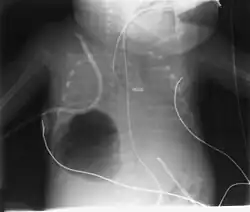

O diagnóstico pode ser feito por radiografia de tórax; a lesão aparece como uma pequena área redonda cheia de ar. A tomografia computadorizada pode fornecer uma compreensão mais detalhada da lesão.[1] Diagnósticos diferenciais – outras condições que podem causar sintomas semelhantes aos da pneumatocele incluem câncer de pulmão, tuberculose[7] e abscesso pulmonar[1] no contexto da síndrome de Hiper IgE (também conhecida como síndrome de Jó) e como uma complicação da pneumonite por COVID-19.[8]